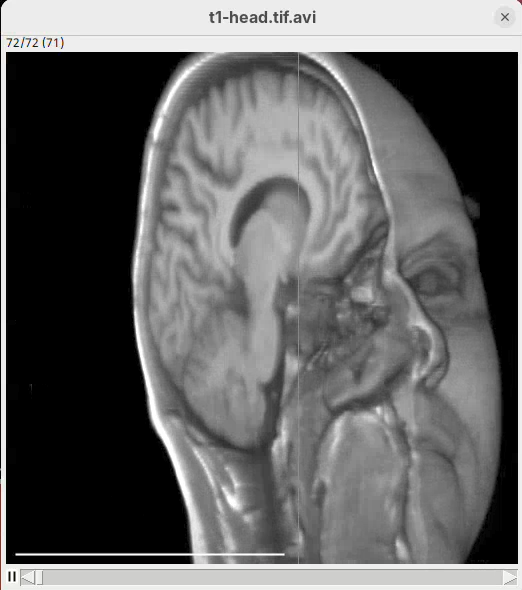

A new window will show up with an image stack of 10 frames containing the generated animation.

- Press play or and watch the head turn 360 degrees during these 10 frames.

Note that we did not need to define how many degrees the head would turn for each frame. We can simply state that we need the head to turn 360 in these 10 frames and 3Dscript will deal with it.

- After the first sentence, write the two commands as shown below:

From frame 0 to frame 35 rotate by 360 degrees horizontally

From frame 36 to frame 71 change channel 1 bounding box min z to 60

From frame 72 to frame 99 change channel 1 bounding box min z to 0- Press

Run.

The script is saying to rotate 360 degrees horizontally, as before, set the Z range minimum to 60 (roughly halfway through the sample) for about 30 frames, and then set the Z range minimum back to 0 in the subsequent 30 frames. And that’s what we get.